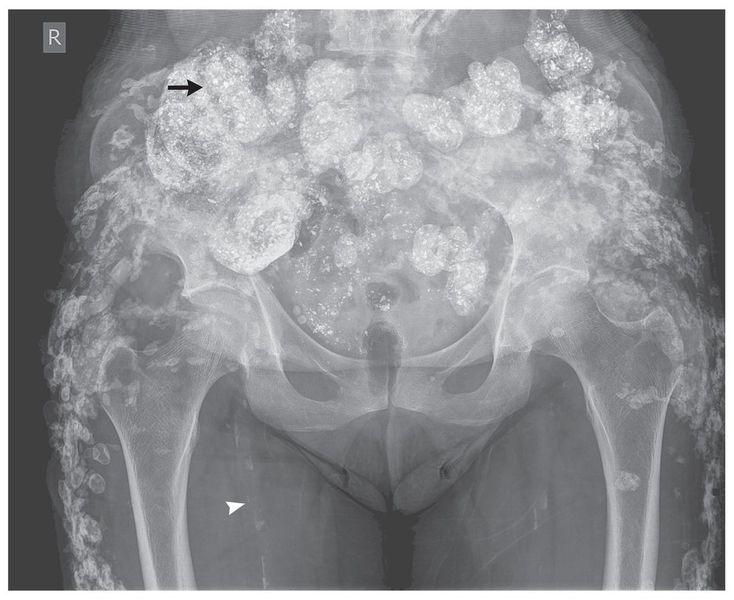

An 80-year-old woman presented with left leg pain. She had end-stage renal disease caused by hypertensive nephrosclerosis and was undergoing maintenance hemodialysis. A radiograph of the pelvis and femur revealed extensive calcifications (arrow) in the muscles and subcutaneous tissues of the lower abdominal wall, gluteal regions, and outer thighs, in addition to vascular calcification (arrowhead) and osteopenia. There was no evidence of fracture. The patient was receiving warfarin because of atrial fibrillation. She also had secondary hyperparathyroidism due to renal failure; a month before the administration of cinacalcet was begun, she had a parathyroid hormone level of 73.1 pmol per liter (normal range, 0.8 to 5.5) and a product of the calcium level times the phosphorus level of 5.2 mmol2 per square liter (65 mg2 per square deciliter; reference range, <4.4 mmol2 per square liter [<55 mg2 per square deciliter]). Secondary hyperparathyroidism, a high calcium–phosphorus product, and warfarin have been associated with metastatic calcification and calcific uremic arteriolopathy (calciphylaxis), especially in patients undergoing dialysis. Warfarin inhibits γ-carboxylation of matrix Gla protein (a protein that inhibits calcification). The administration of warfarin was stopped, and aggressive management of calcium and phosphorus levels was continued. Although the biochemical variables improved, the patient continues to have pain, which is a notable feature of calcific uremic arteriolopathy. Attempts to manage her pain continue.